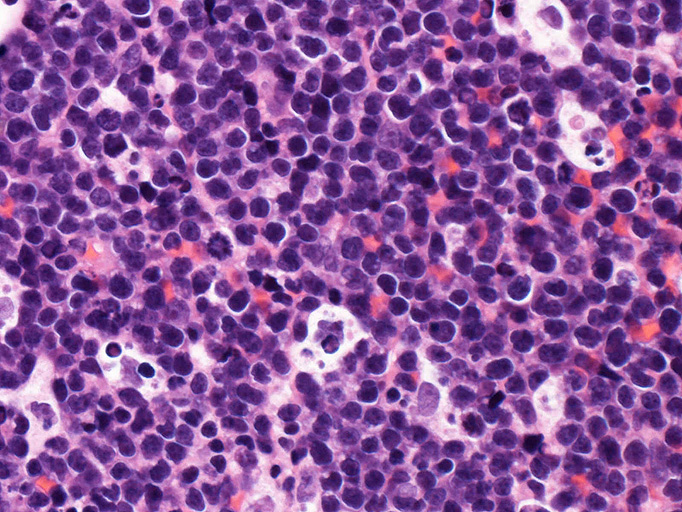

Burkitt lymphoma

Burkitt's lymphoma--症例01

組織・細胞病理所見

エコーガイド下肝腫瘤針生検組織

尾状葉の腫瘍から16G, 11mm穿刺針で5mm, 2mmの組織を採取した。2mmの組織は線維組織と肝組織で腫瘍細胞を含んでいなかった。穿刺針洗浄液をkaryotypeに提出する。